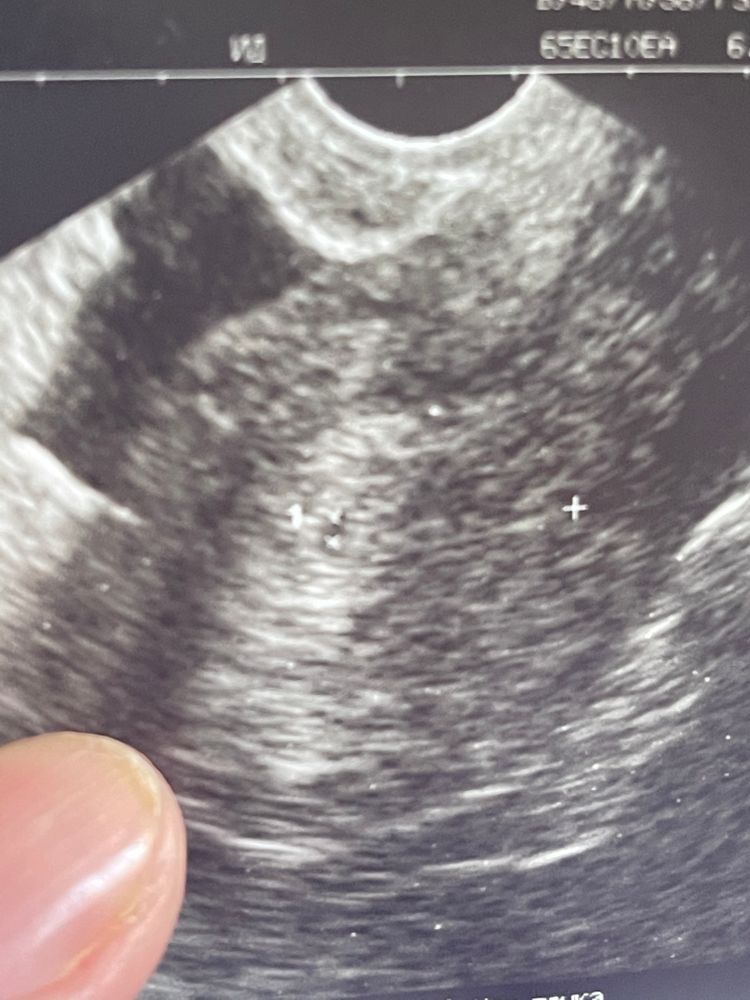

УЗИ диагностика ранней беременности.

Вопросы про УЗИ, обследования и анализы: что, где, как, когда?В субботу была на узи.По месячным срок 5 недель, по овуляции 3 недели. Ничего она там не увидела, только ровное круглое образование размером 2,2 мм. И то не факт говорит, что это беременность😓Контроль узи через 2 недели. На фото с узи где цифра 1 видно это маленькое образование.

У меня тоже срок 5.1. Вчера на узи нашли пя 4.5 мм,но я не знаю какой дпо, но хгч 1500 был. Возможно у вас поменьше.